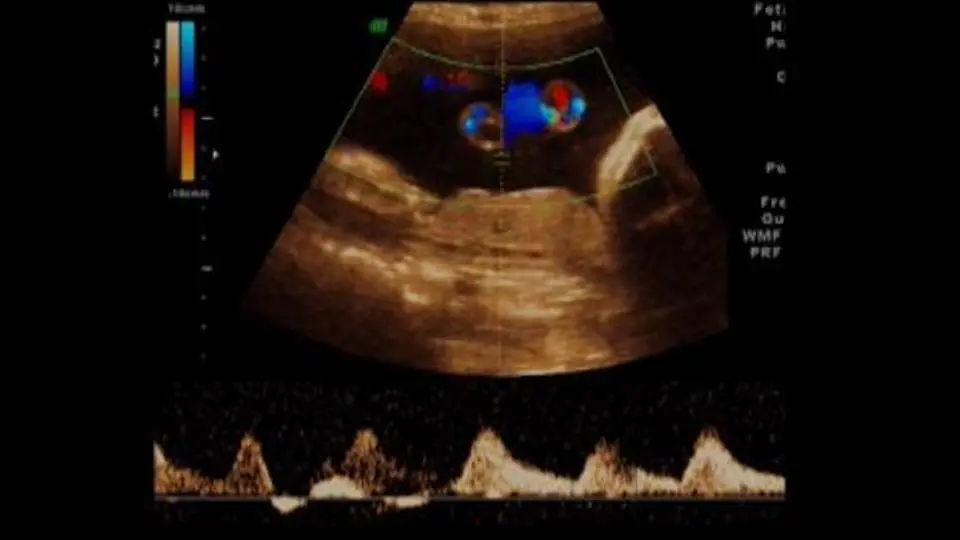

Eine Insertio Velamentosa kann während einer Ultraschalluntersuchung während der Schwangerschaft festgestellt werden. Ein Ultraschall kann die Position der Nabelschnurgefäße und die Plazenta zeigen. In einigen Fällen kann eine Insertio Velamentosa erst während der Geburt festgestellt werden.

- Regelmäßige Ultraschalluntersuchungen : Regelmäßige Ultraschalluntersuchungen können die Gesundheit des Babys überwachen und frühzeitig Anzeichen von Komplikationen erkennen.